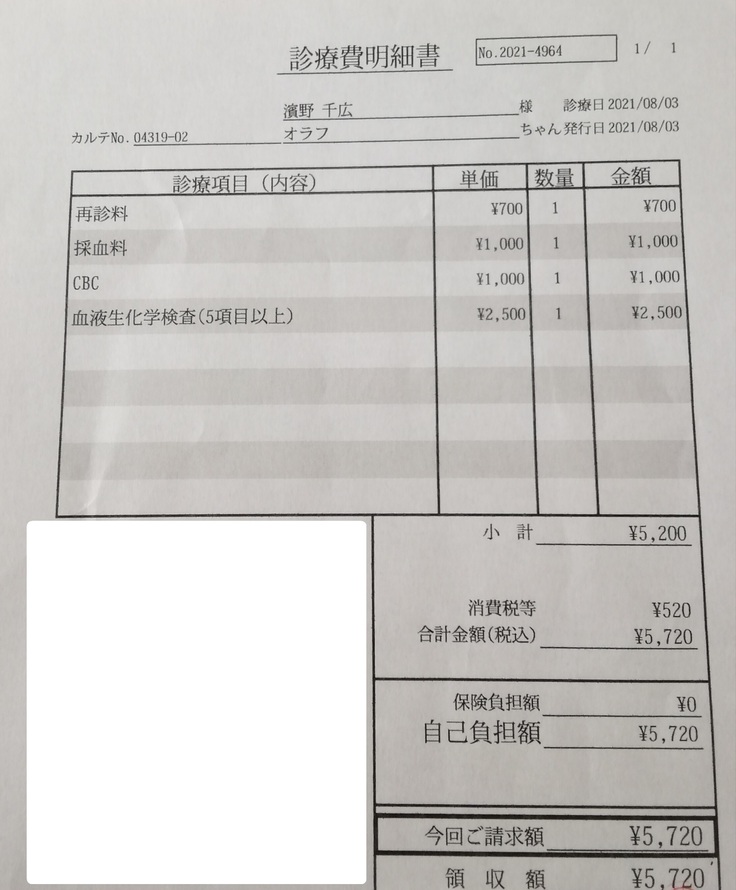

FIP陽性が確定し、オラフの動きは悪くはなかったんですが、食欲は戻らなかったので再度B病院に行きました。

熱が40度あり、体重が3.3kg→3.0kgまで減っていました。

血液検査の結果も前回より貧血値やA/G比が悪くなっていました。

「新薬に切り替えたほうがいいです。」と言われました。

そしてこの日からオラフの84日間の投薬が始まりました。

検査費と薬代です。